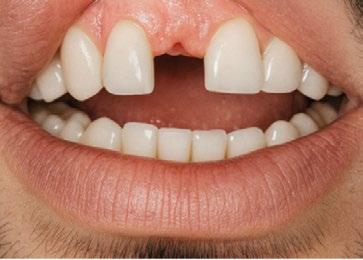

En 1987 y a pesar de que las rehabilitaciones unitarias no ferulizadas eran aún consideradas experimentales, tratamos a dos pacientes jóvenes no fumadores que habían perdido un solo diente.

El primero de nuestros pacientes, de 32 años, había perdido su incisivo central superior derecho a los 12 años y el segundo, de 29 años, había perdido su incisivo lateral superior izquierdo en un accidente de tráfico ocurrido siete años antes. (Figura 4)